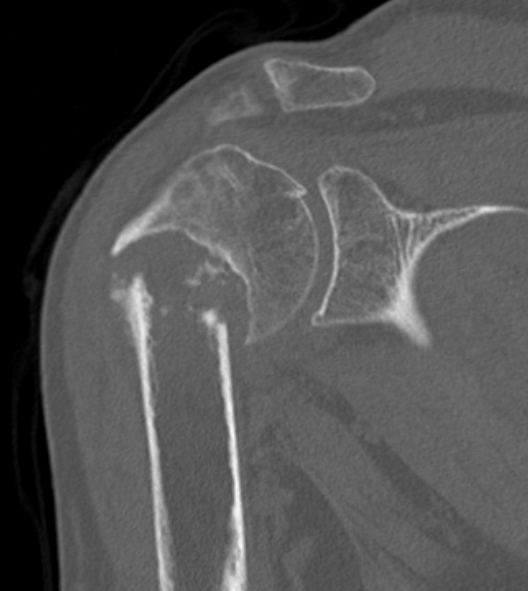

Deforming Forces

| 2 part fracture | Greater tuberosity fracture | Lesser tuberosity fracture |

|---|---|---|

|

Pectoralis major displaces shaft medially Head internally rotated by SSC |

Fragment pulled postero-superior Combination of supraspinatus / infraspinatus / Teres minor |

Displaced medially by subscapularis |